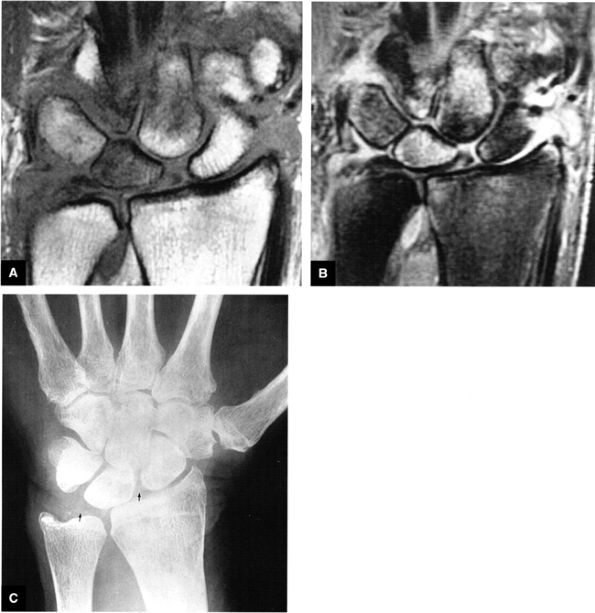

At the site of the radiolunate articulation, the distal articular surfaces of the radius and ulna are usually at the same level (i.e., neutral ulnar variance). Alternatively, the ulna may be relatively long (positive ulnar variance), leading to an ulnar abutment syndrome, or relatively short (negative ulnar variance), as is often seen in Kienböck's disease. The distal radius forms two facets that articulate with the scaphoid and lunate of the proximal carpal row. This articulation of the proximal pole of the scaphoid in the scaphoid fossa is quite congruent, and even a small degree of malrotation of the scaphoid may cause incongruent loading of the articular cartilage and subsequent degeneration (such as that which accompanies a SLAC wrist, as described by Watson and Ryu37). The lunate facet commonly becomes incongruent following distal radius fractures, especially die-punch-type fractures. The interosseous ligaments join the proximal carpal bones at their proximal edges.36